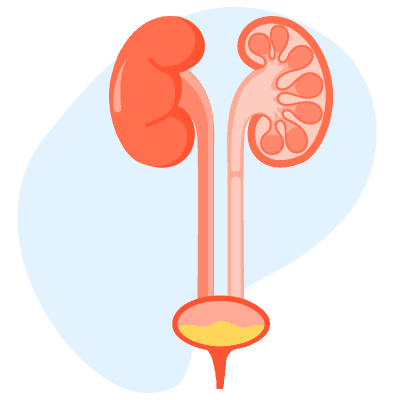

အမျိုးသားတွေဟာ အသက်ကြီးလာတာနဲ့အမျှ ဆီးကျိတ် နဲ့ ပတ်သက်တဲ့ ပြဿနာတွေ ဖြစ်နိုင်ခြေများလာလေ့ရှိပါတယ်။ ဆီးကျိတ်ရောင်တာက စလို့ ဆီးကျိတ်ကင်ဆာအထိ အမျိုးမျိုးဖြစ်နိုင်ပါတယ်။ ဆီးကျိတ်ရောဂါလက္ခဏာတွေကို သိရှိဖို့နဲ့ ဆီးကျိတ် ကျန်းမာရေး ကောင်းစေဖို့ နေထိုင်စားသောက်နည်းတွေကို သိထားသင့်ပါတယ်။ အဖြစ်များတဲ့ ဆီးကျိတ်ရောဂါများ ဆီးကျိတ်ရောင်ရမ်းခြင်း ဆီးကျိတ်ရောင်ရမ်းတာက ဘယ်အရွယ်မှာမဆို ဖြစ်နိုင်ပေမယ့် ငယ်ရွယ်တဲ့အမျိုးသားတွေ (၃၀-၅၀ကြား)တွေမှာ ပိုဖြစ်တတ်ပါတယ်။ ဆီးကျိတ်ရောင်ခြင်းမှာ -ဘက်တီးရီးယားကြောင့် ရောင်ရမ်းခြင်းနဲ့ -ဘက်တီးရီးယားကြောင့် မဟုတ်ဘဲ တခြားအကြောင်းအရင်းကြောင့် ရောင်ရမ်းခြင်း ဆိုပြီး ၂မျိုးရှိပါတယ်။ လက္ခဏာအနေနဲ့ -ခဏခဏ ဆီးသွားချင်တာ -ဆီးကျန်တာ -ချမ်းတုန်ဖျားတာ -ဆီးပူဆီးကျဉ်တာတွေ ဖြစ်တတ်ပါတယ်။ ဆီးကျိတ်ကြီးခြင်း ကင်ဆာမဟုတ်တဲ့ ရိုးရိုးဆီးကျိတ်ကြီးခြင်းက အသက်ကြီးလေ ဖြစ်နိုင်ခြေ များလေလေပါ။ အသက် ၅၀ဝန်းကျင်ဆို အမျိုးသား၂ယောက်မှာ ၁ယောက် ဖြစ်နိုင်ခြေရှိပါတယ်။ အသက် ၆၀ကျော်လာရင်တော့ ဖြစ်နိုင်ခြေက ၇၅% ထိတက်လာပါတယ်။ လက္ခဏာအနေနဲ့ -ဆီးသွားရခက်တာ -ဆီးညှစ်ပေါက်ရတာ -ဆီးလုံးသေးတာ -ဆီးမထိန်းနိုင်တာ -ခဏခဏ ဆီးသွားချင်တာ -ဆီးကျန်ပြီး တစ်စက်စက်နဲ့ ကျနေတာတွေ ဖြစ်နိုင်ပါတယ်။ ဆီးကျိတ်ကင်ဆာ အမျိုးသားတွေ အဖြစ်အများဆုံးကင်ဆာတွေထဲမှာ ဒုတိယနေရာမှာ […]